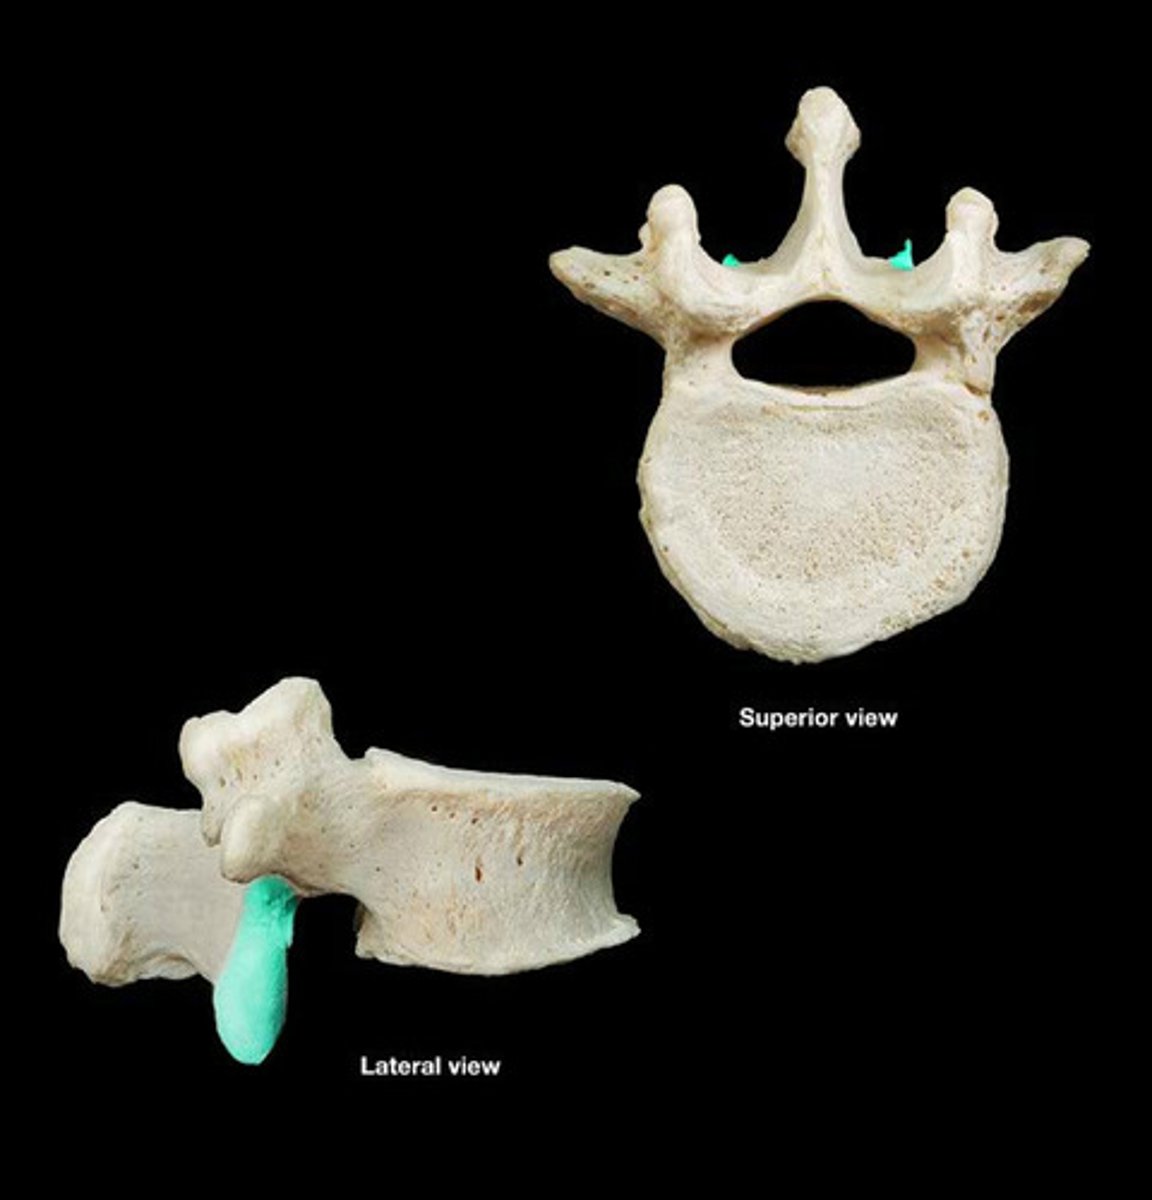

spinous process

inferior articular process

transverse costal facet

rib articulation (attachment) ONLY FOUND IN T1-T12

what is the purpose of the transverse costal facets

Inferior vertabral notch (intra vertabral foreman)

transverse costal facets (articulations) where ribs attach to

what differenciates the T spine vertebra